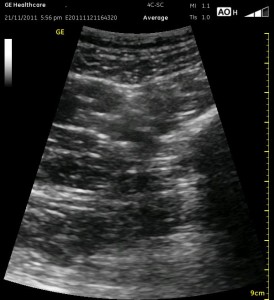

The image above is not an obvious one, and I did that on purpose. You have to get used to the idea that you will not always have a ‘super distinct’ image with this approach, and you will often need to use a number of additional clues to find your target and then to put local around it. I think the only way to really get a handle on being able to identify the basic elements is to look at several images over and over, so I have provided several below for you to use for practice. Note that the sciatic nerve will ‘poke out’ from behind the femur to different degrees depending on your orientation to the femur as well as to how far up or down the femur you go. It will be seen more if you are proximal. See how well you can identify the structures in the images below.